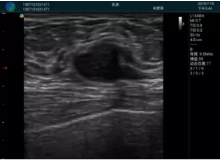

頸動(dòng)脈血流充盈飽滿(mǎn),無(wú)外溢

肝內(nèi)血管顯示清晰,血流敏感無(wú)外溢

甲狀腺囊性結(jié)節(jié),囊壁鈣化,透聲好

甲狀腺囊性占位